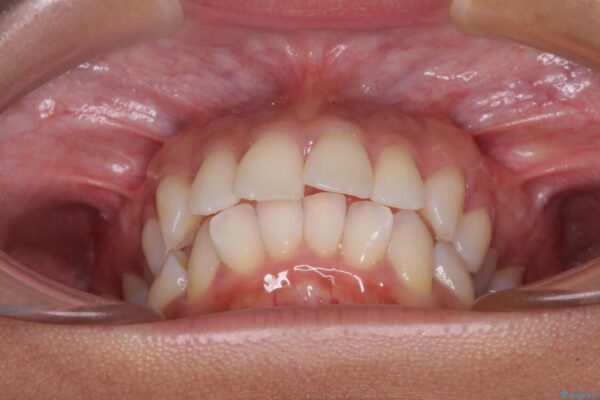

下唇が突き出るような口元の突出感が気になるとのことで来院された患者様です。

上下顎ともに前突した歯列であったので、上下ともに左右の第1小臼歯4本を抜歯し、ワイヤー装置にて矯正治療を行うこととしました。

治療前

• 抜歯矯正で唇を閉じやすく 目立たないワイヤー装置 治療前画像